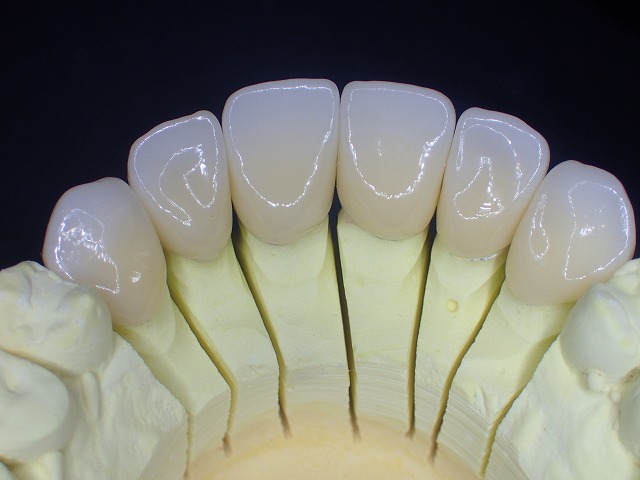

技工物完成 奥歯で咬む位置を設定した状態で

技工物にも計測した

水平 垂直が写して

描記してありますが、実際にお口装着すると

多少のズレがありますので、お口の中で

ジルコニアの形態を修正します。

マルチレイヤージルコニア

先端は白く透明

歯頚部は色が濃く

天然の歯のようにグラデーションがあります。